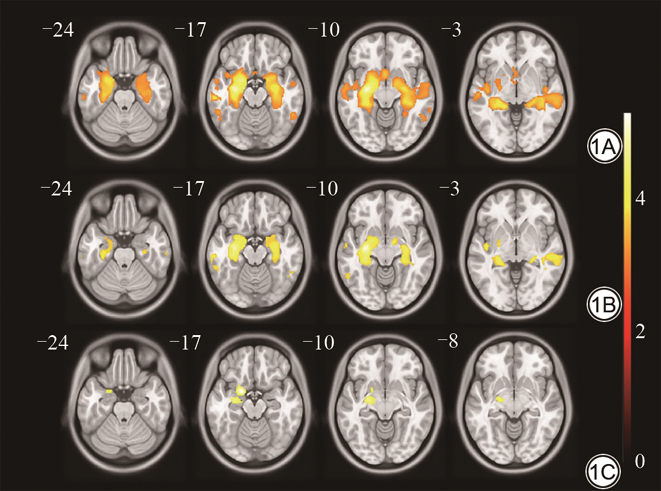

三组间全脑灰质体积的差异有统计学意义(P<0.05),组间比较结果如图1所示。NC组和AD组间存在明显差异,包括双侧POC、海马、海马旁回、杏仁核、颞上回、颞中回、颞下回等结构(FWE多重比较校正,P<0.01,t=5.56);MCI组和AD组间差异主要包括双侧POC、海马、海马旁回、杏仁核等结构(FWE多重比较校正,P<0.01,t=5.55);NC组和MCI组间差异主要包括左侧POC、海马、杏仁核等结构(FDR多重比较校正,P<0.05,t=4.66)。

三组间双侧POC灰质体积的差异均有统计学意义(FWE多重比较校正,P<0.01),NC组双侧POC灰质体积均明显大于AD组,组间比较结果详见图2。三组间左侧海马灰质体积的差异均有统计学意义(Bonferroni校正,P<0.05);NC组和AD组、MCI组和AD组间右侧海马、双侧杏仁核、双侧岛叶、右侧眶额皮质灰质体积的差异均有统计学意义(Bonferroni校正,P<0.05),上述结构在NC组和MCI组间的差异无统计学意义(Bonferroni校正,P>0.05);左侧眶额皮质灰质体积在NC组和AD组间的差异有统计学意义(Bonferroni校正,P<0.05),在MCI组和AD组、NC组和MCI组间的差异无统计学意义(Bonferroni校正,P>0.05)。统计结果详见表2。